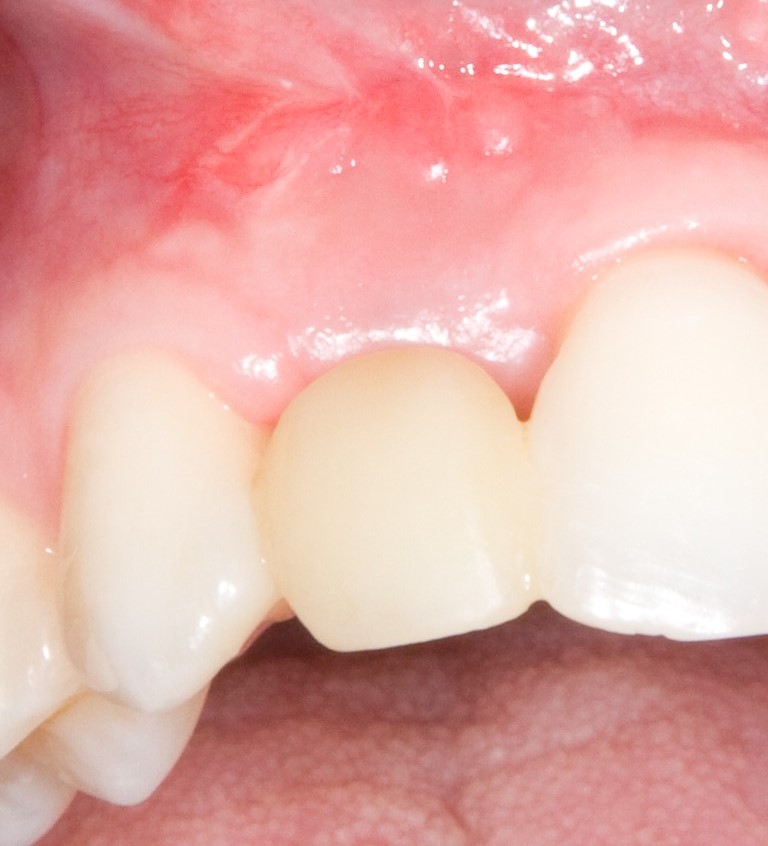

В таких случаях пациенту нередко предлагается какая-то съемная протетическая конструкция (в народе называемая «бабочкой» или «жучком»), задача которой — замаскировать отсутствие зуба до его восстановления с помощью импланта:

И, я должен заметить, что с маскировкой такой простейший протез отлично справляется: